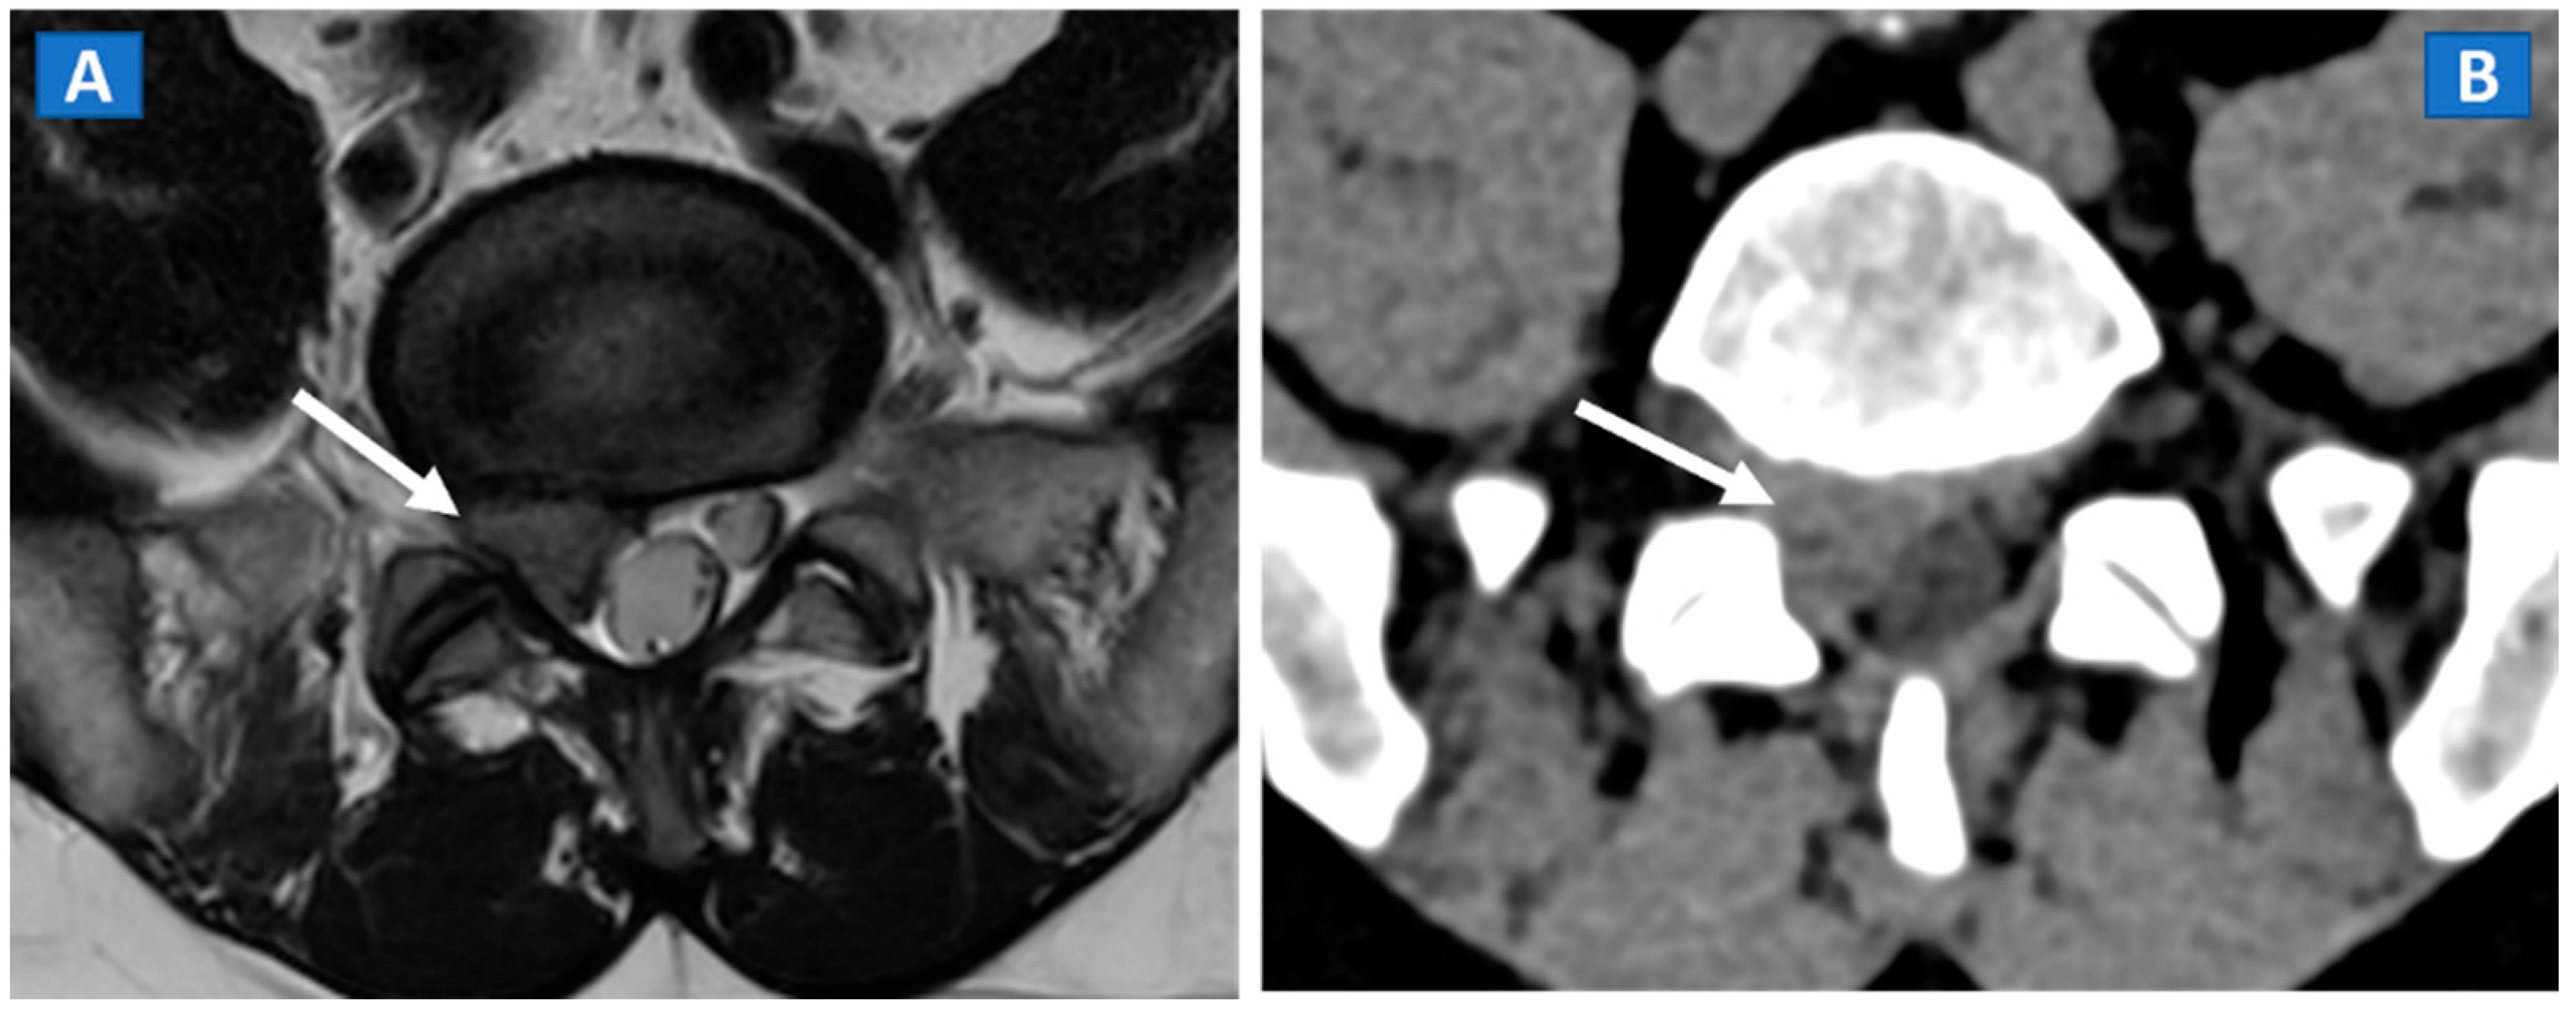

10. Inflammatory Disorders